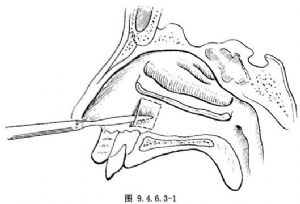

2.在下鼻甲前端之後約1cm的下鼻道外側壁處做一垂直切口,於此切口後1.5~2.0cm處做另一垂直切口,於兩垂直切口上下做兩平行切口分離骨膜除去黏膜片,暴露下鼻道骨壁(圖9.4.6.3-1)。亦可於兩垂直切口之上做一個平行切口,保留黏膜片,開窗後將黏膜片翻於竇腔內。